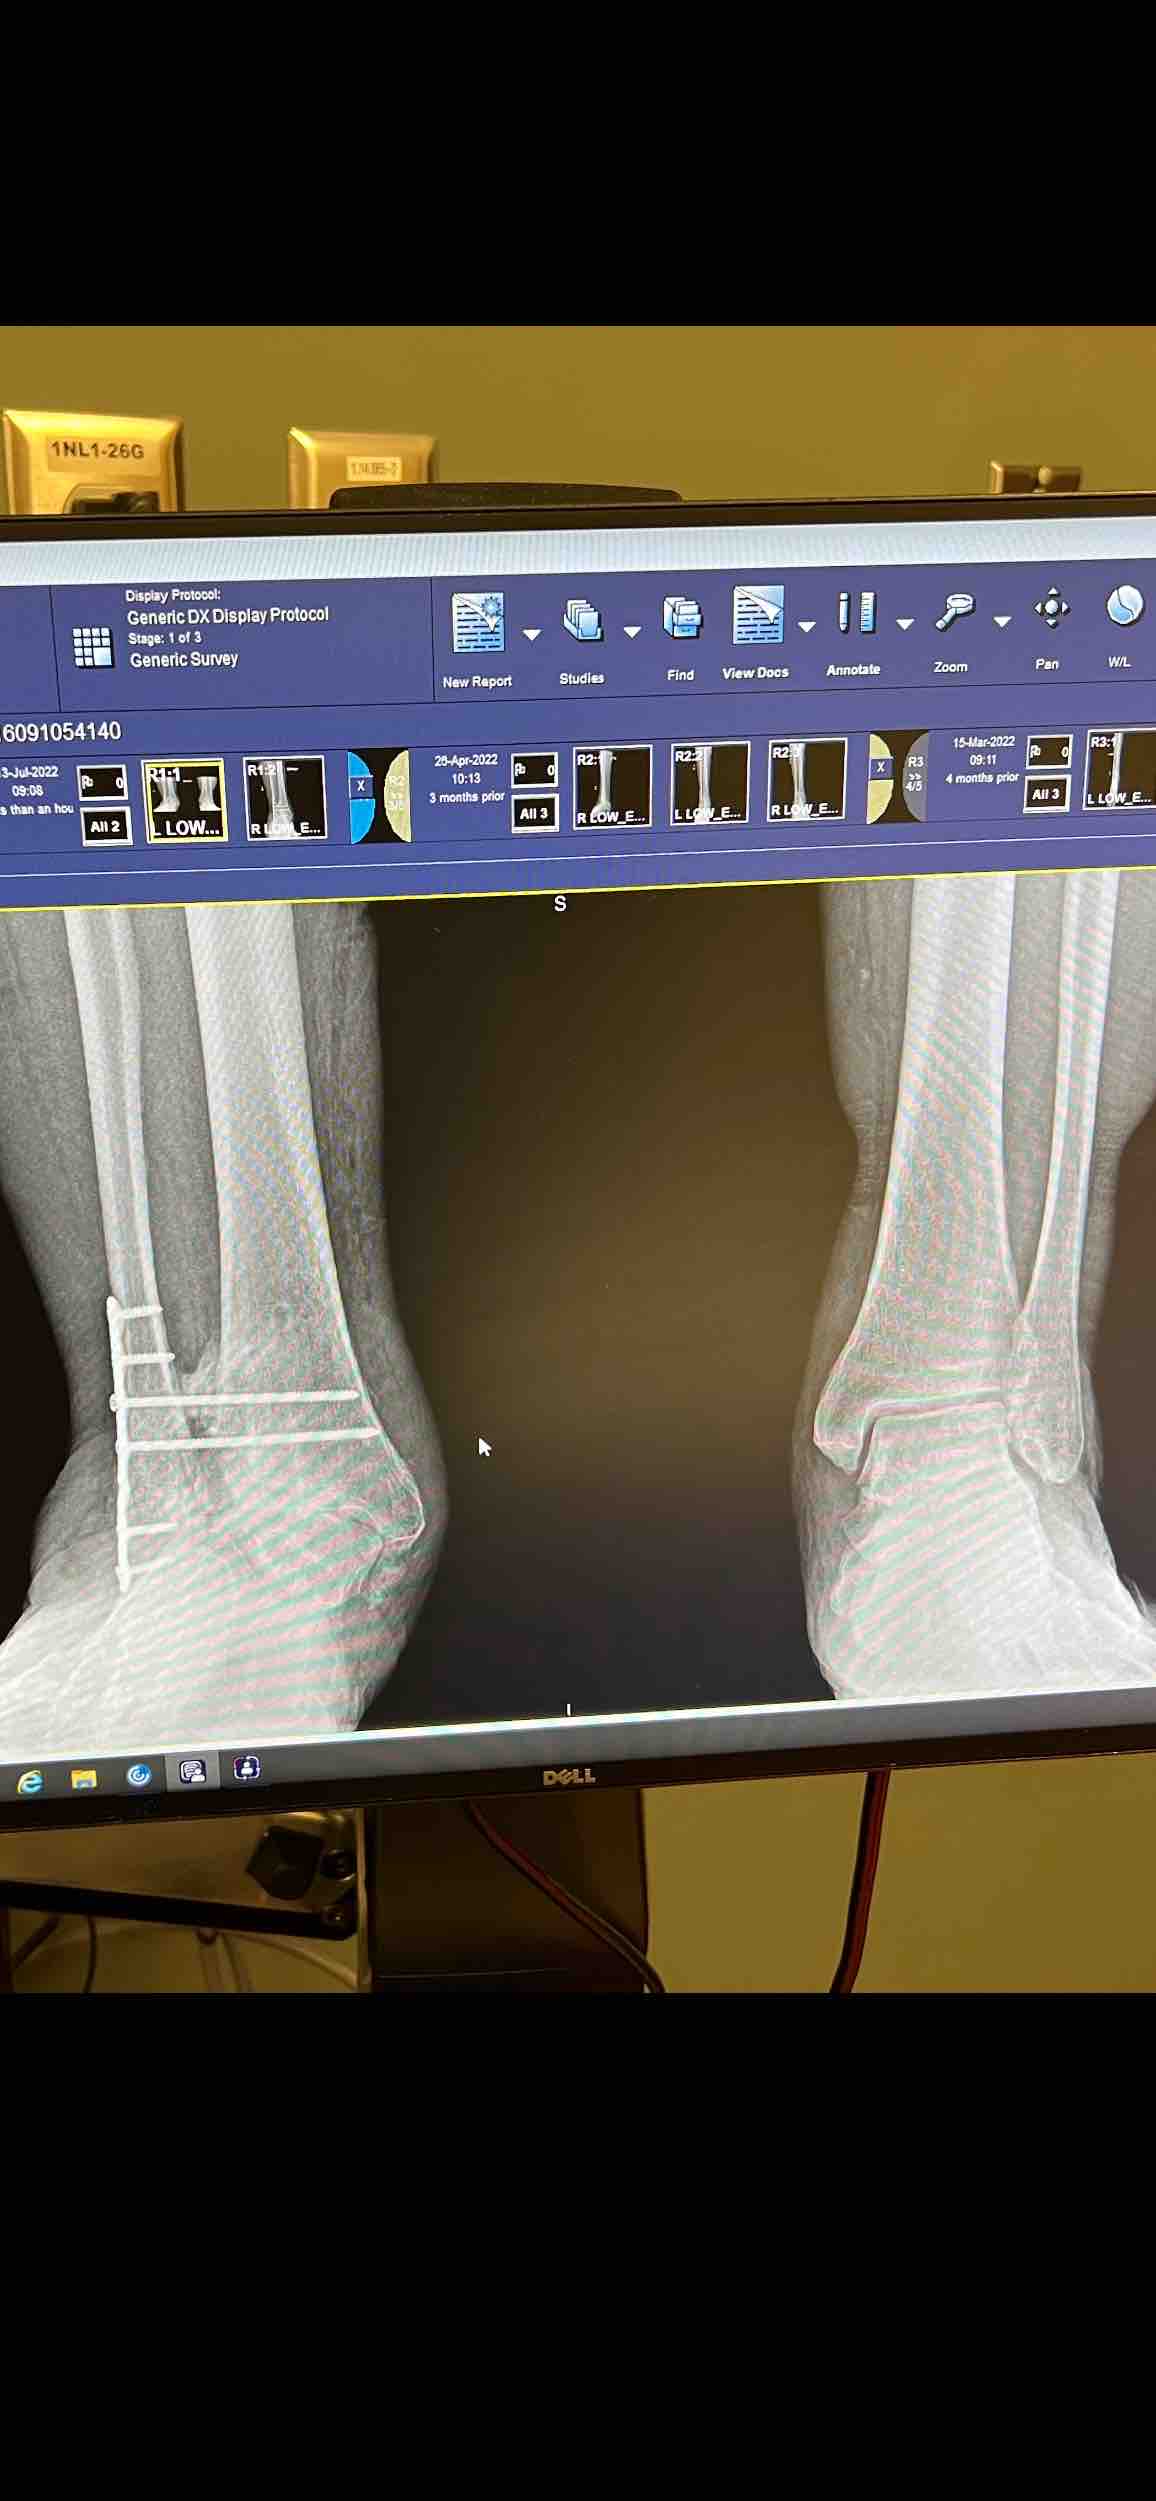

Here is a picture of my x-ray so you can see what’s wrong with my ankle.

That is bone rubbing and crushing bone with every step I take.